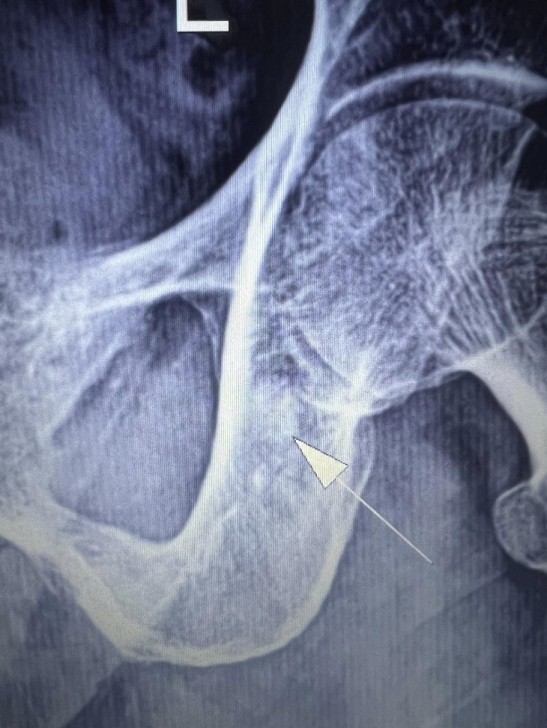

AFN.az xəbər verir ki, tanınmış həkim Aydın Əliyev bu sahədə vəziyyətin getdikcə ağırlaşdığını bildirib. O, xəstələrdən birinin müayinə nəticələrini paylaşaraq bunları yazıb: “Onkoloji xəstəliklərin müayinə və müalicəsinin hələ də icbari tibbi sığorta tərəfindən qarşılanmamasının daha bir qurbanı. Sağ qamış sümüyündəki törəmənin maddi imkansızlıq səbəbindən vaxtında və sistemli müalicə və ya əməliyyat edilməməsi səbəbindən fəqərələrə, qabırğalara, kürək, çanaq sümüklərinə, ağciyərə çoxsaylı metastazları. Demək olar ki, adam həyatını itirib”.